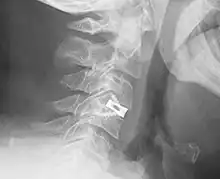

X-ray of interbody fusion cage in cervical vertebrae, Juliet system.